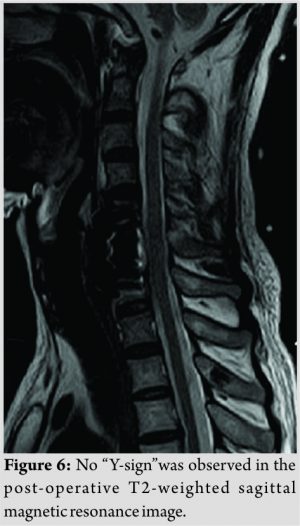

We performed a CSF lumbar drainage after operation to reduce the CSF leakage in the neck. The muscle strength of the left upper and lower limbs of the patient was completely recovered to 5/5 immediately after surgery, while sensory deficits on the right side of the body existed for 3 months. Pathological analysis of the removed fragments confirmed fibrocartilaginous tissue and degenerative disc diagnosis. The height of anterior and middle columns was restored on the post-operative plain radiographs and CT scans (Fig.5). No “Y-sign” was observed on the post-operative T2-weighted sagittal MRI any more (Fig. 6). The patient proposed no complaint during the post-operative follow-up.